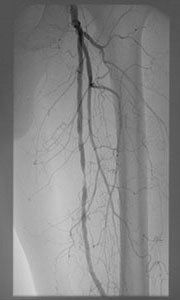

静脈のカテーテル治療

深部静脈血栓症(DVT)という病気があります。これは静脈という全身から心臓に戻ってくる血管に血栓ができ閉塞することにより、下肢の浮腫、発赤、疼痛といった症状が出現し、人によってはその血栓が肺動脈に飛び肺塞栓症という命にかかわる病気につながることもあります。通常は抗凝固薬という血栓を徐々に溶かす内服薬を服用しますが、完全に閉塞した血管の中には薬剤が到達しにくく、症状の改善には数か月を要す場合が多く、これにより血栓後後遺症という、下肢の浮腫、だるさ、ひどい場合には皮膚の潰瘍などの後遺症を残すことがあります。当院ではカテーテル血栓溶解療法(CDT)と呼ばれる、血栓の中に細いカテーテルを留置し血栓溶解剤を直接血栓に向け噴射する治療を以前から積極的に行っております。これにより多くの場合は血栓の早期の溶解が得られ、自覚症状が大幅に早く改善し、血栓後後遺症を減らすことができます。深部静脈血栓症(DVT)の方全員が適応となるわけではなく、症状が強い場合に限定される治療です。

血栓内に留置し、多方向に血栓溶解剤を直接噴射し血栓を溶かすことができる血栓溶解用カテーテル

(画像提供:メリットメディカル社)